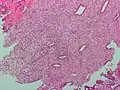

(A) proliferative endometrium (Left: HE × 400) and proliferative endometrial cells (Right: HE × 100)

(B) secretory endometrium (Left: HE × 10) and secretory endometrial cells (Right: HE × 10)

(C) atrophic endometrium (Left: HE × 10) and atrophic endometrial cells (Right: HE × 10)

(D) mixed endometrium (Left: HE × 10) and mixed endometrial cells (Right: HE × 10)

(E): endometrial atypical hyperplasia (Left: HE × 10) and endometrial atypical cells (Right: HE × 200)

(F) endometrial carcinoma (Left: HE × 400) and endometrial cancer cells (Right: HE × 400).

Chorionic tissue can result in marked endometrial changes, known as an Arias-Stella reaction, that have an appearance similar to cancer.[15] Historically, this change was diagnosed as endometrial cancer and it is important only in so far as it should not be misdiagnosed as cancer.